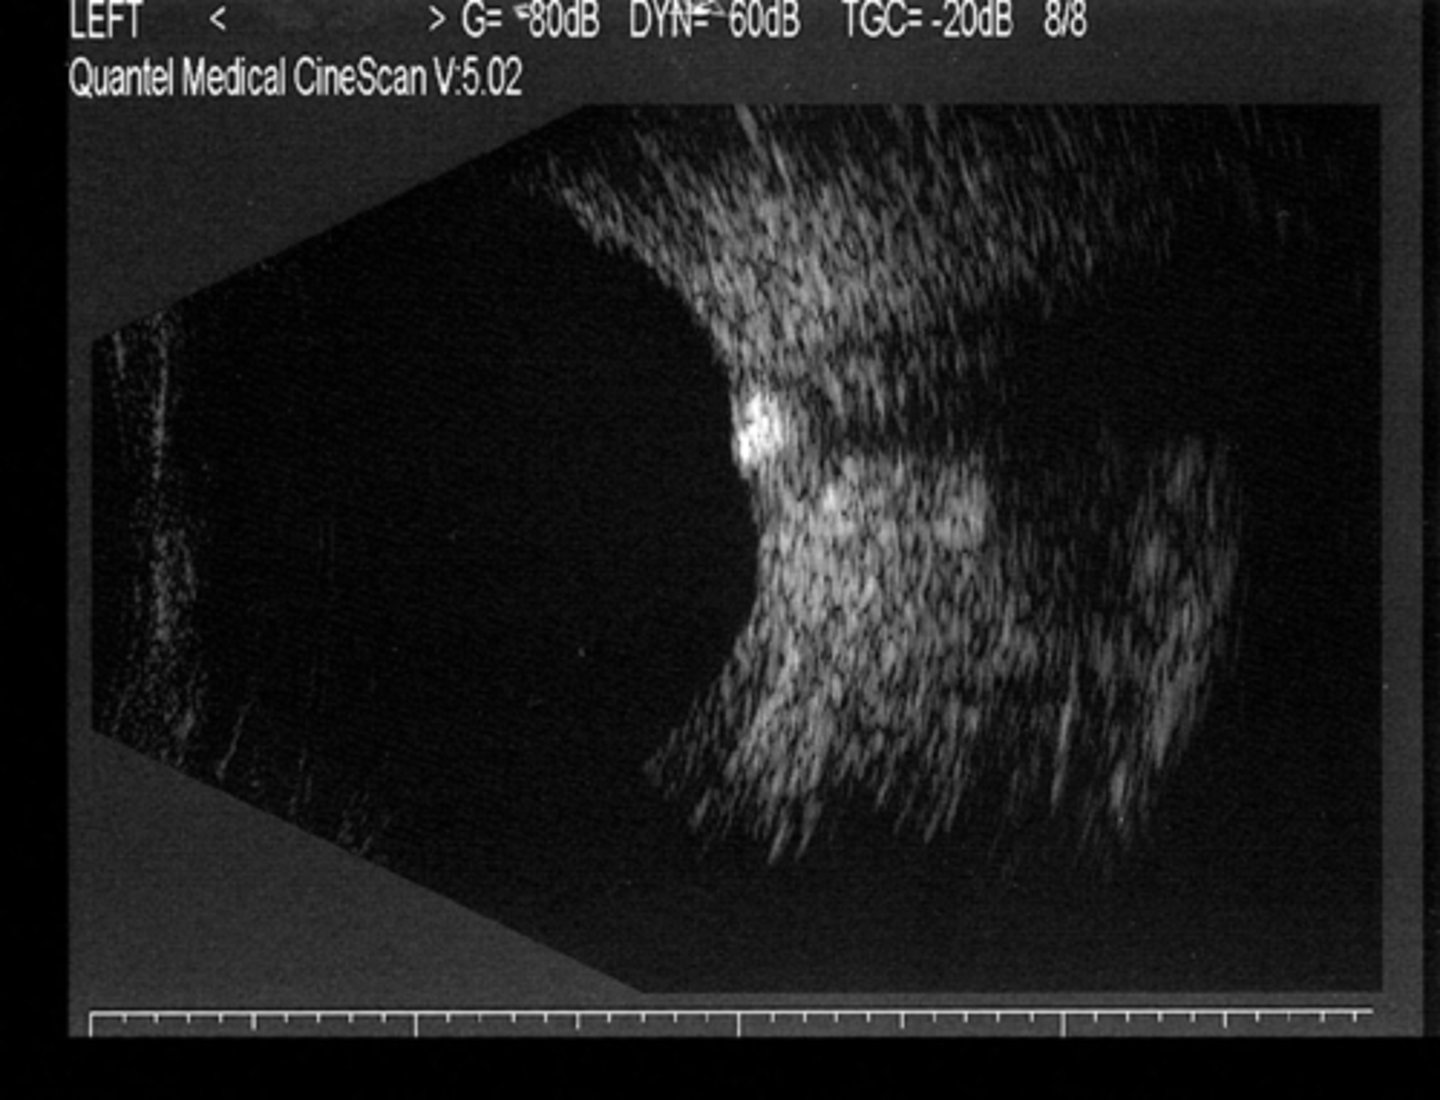

How do disc drusen appear on B scan?

hyper-reflective if calcified